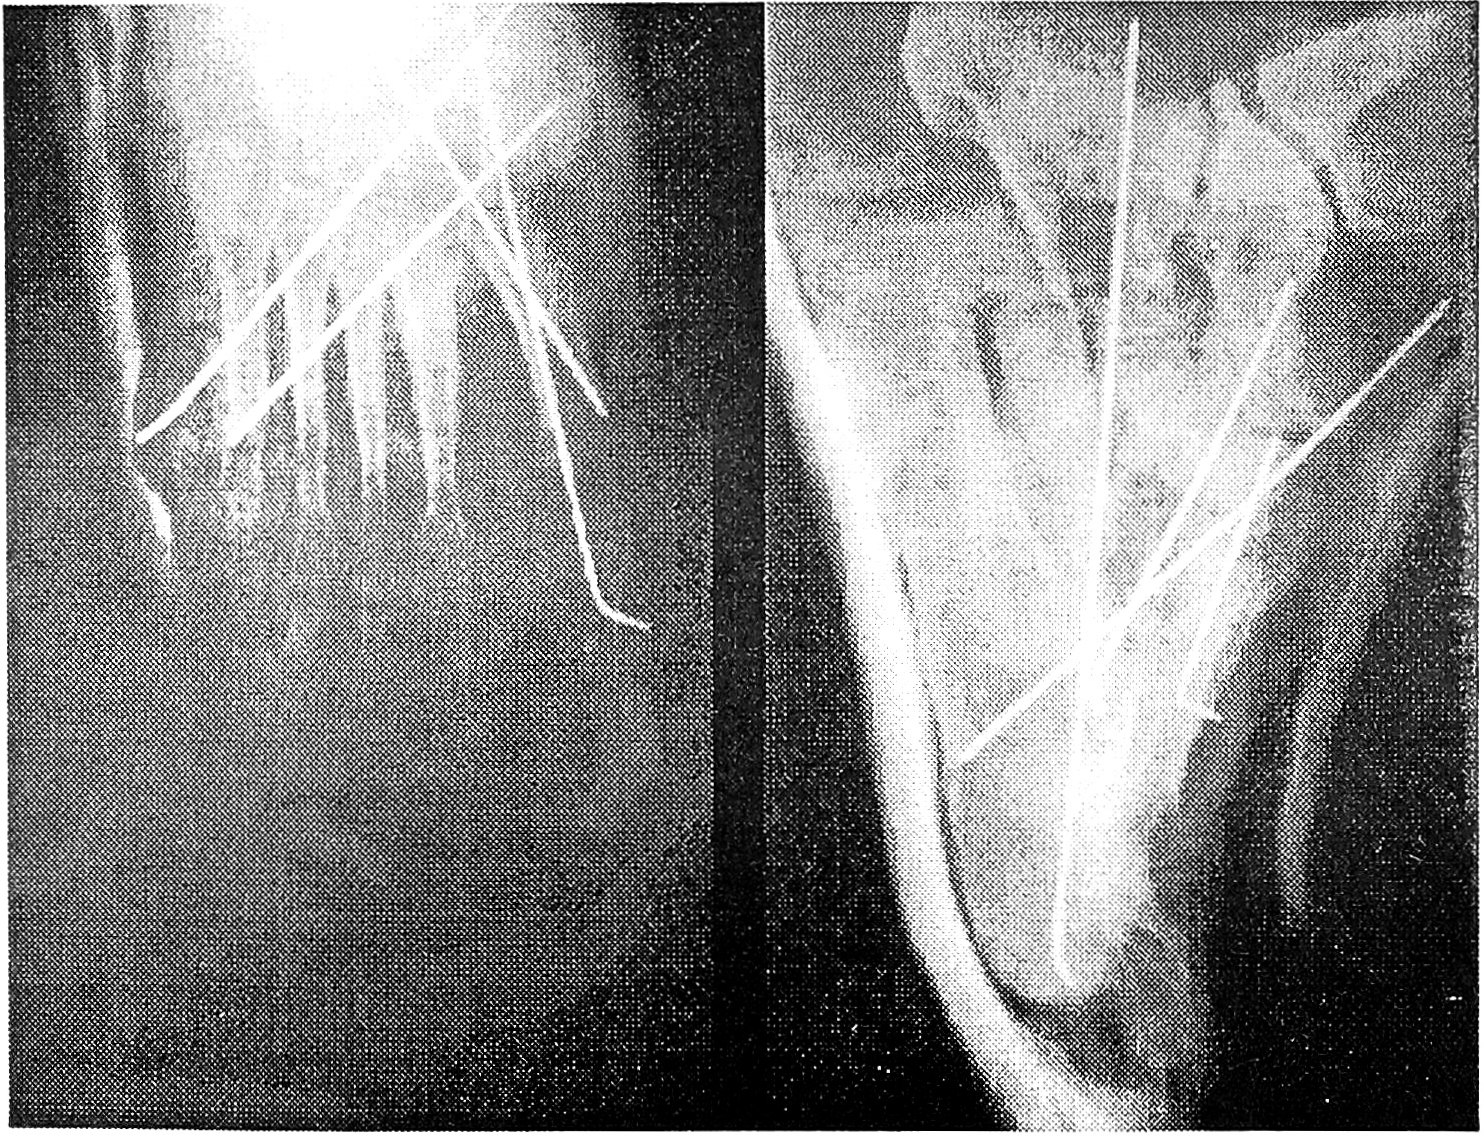

Больная П., 42 лет, поступила в 1-е отделение ЦИТО с диагнозом: застарелый переломовывих в суставе Лисфранка левой стопы (см. рис. 1 на вклейке). 13.12.92 резко подвернула левую ногу, в результате чего получила дивергирующий переломовывих в суставе Лисфранка. Своевременно правильный диагноз поставлен не был, лечилась гипсовой лонгетой. После снятия гипсовой повязки обнаружена деформация внутреннего отдела стопы, которая в дальнейшем прогрессировала. При поступлении отмечается выраженная деформация переднего и среднего отделов стопы. Внутренний край стопы опущен, в среднем отделе прощупывается опухолевидное образование костной плотности, при пальпации болезненное; наружный край стопы несколько приподнят, стопа укорочена. Больная не может носить обычную обувь. В ЦИТО 5.02.93 проведен первый этап операции — наложен аппарат Илизарова, с помощью которого устранены все виды деформации (см. рис. 2 на вклейке). Стопа приняла нормальную форму, появились контуры внутреннего свода. Через 2 нед аппарат снят, произведен частичный артродез сустава Лисфранка в виде двойного замка — между дистальными концами I и II плюсневых костей и проксимальными концами I и II клиновидных костей, а также между основанием V плюсневой и кубовидной костью. Закончена операция трансартикулярной фиксацией спицами Киршнера (см. рис. 3 на вклейке), наложен гипсовый сапожок, в подошвенную часть которого вгипсован металлический супинатор с высоким сводом для формирования внутреннего свода стопы и профилактики плоскостопия. Спицы удалены через 6 нед, гипсовая иммобилизация продолжалась в течение 3 мес. После снятия гипсовой повязки больная 8 мес носила ортопедическую обувь. Осмотрена через год (см. рис. 4 на вклейке). Жалоб нет, ходит в обычной обуви.

Рис. 1. Рентгенограммы больной П. до операции в прямой и боковой проекции. Виден застарелый дивергирующий переломовывих в суставе Лисфранка.

Рис. 2. В аппарате Илизарова после первого этапа лечения.

Рис. 3. После второго этапа лечения. Видны металлические спицы, проведенные трансартикулярно через передний и средний отделы стопы.